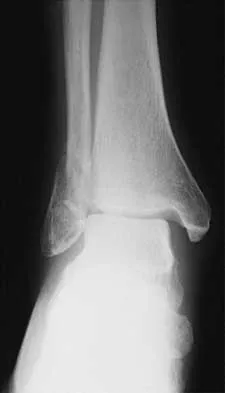

A 57-year-old man has had right ankle pain for the past 10 months following an injury that went untreated. Radiographs are shown in Figures 30a through 30c. Management should consist of

Explanation

The radiographs reveal a malunited distal fibular fracture with shortening. Because there appears to be an adequate cartilage space within the ankle joint, the role of reconstruction would be to prevent arthrosis and the need for ankle arthrodesis, as well as to decrease symptoms. The treatment of choice is restoration of fibular length, alignment, and rotation with osteotomy plating, and bone grafting as needed. There is no indication for ligament reconstruction of a mechanically stable ankle, and tibial shortening osteotomy will not assist in correcting the deformity. Cast immobilization may assist with improvement of symptoms but will not correct the overall process. Determination of fibular length is best done by comparing the talocrural angle of the injured side with the uninjured side. The goal is to perfectly reduce the talus in the ankle mortise. Marti RK, Raaymakers EL, Nolte PA: Malunited ankle fractures: The late results of reconstruction. J Bone Joint Surg Br 1990;72:709-713. Geissler W, Tsao A, Hughes J: Fractures and injuries of the ankle, in Rockwood CA Jr, Green DP, Bucholz RW, Heckman JD (eds): Rockwood and Green's Fractures in Adults, ed 4. Philadelphia, PA, Lippincott-Raven, 1996, pp 2201-2206.